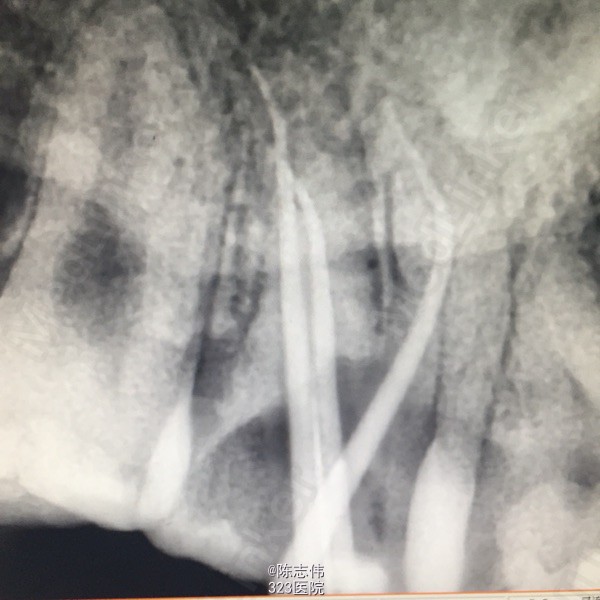

17颊侧大面积龋损,缺损及龈下2mm,探(++) 叩(+) 冷(++) 松动(-)

17,45缺损及髓,根尖无明显异常

17,45慢性牙髓炎

17,45RCT+桩+冠

处理:局麻下16,17,45去龋,16龋净未露髓,清理干燥隔湿后垫底+3M树脂充填。17,45揭开髓室顶,丁香油棉开放,降颌